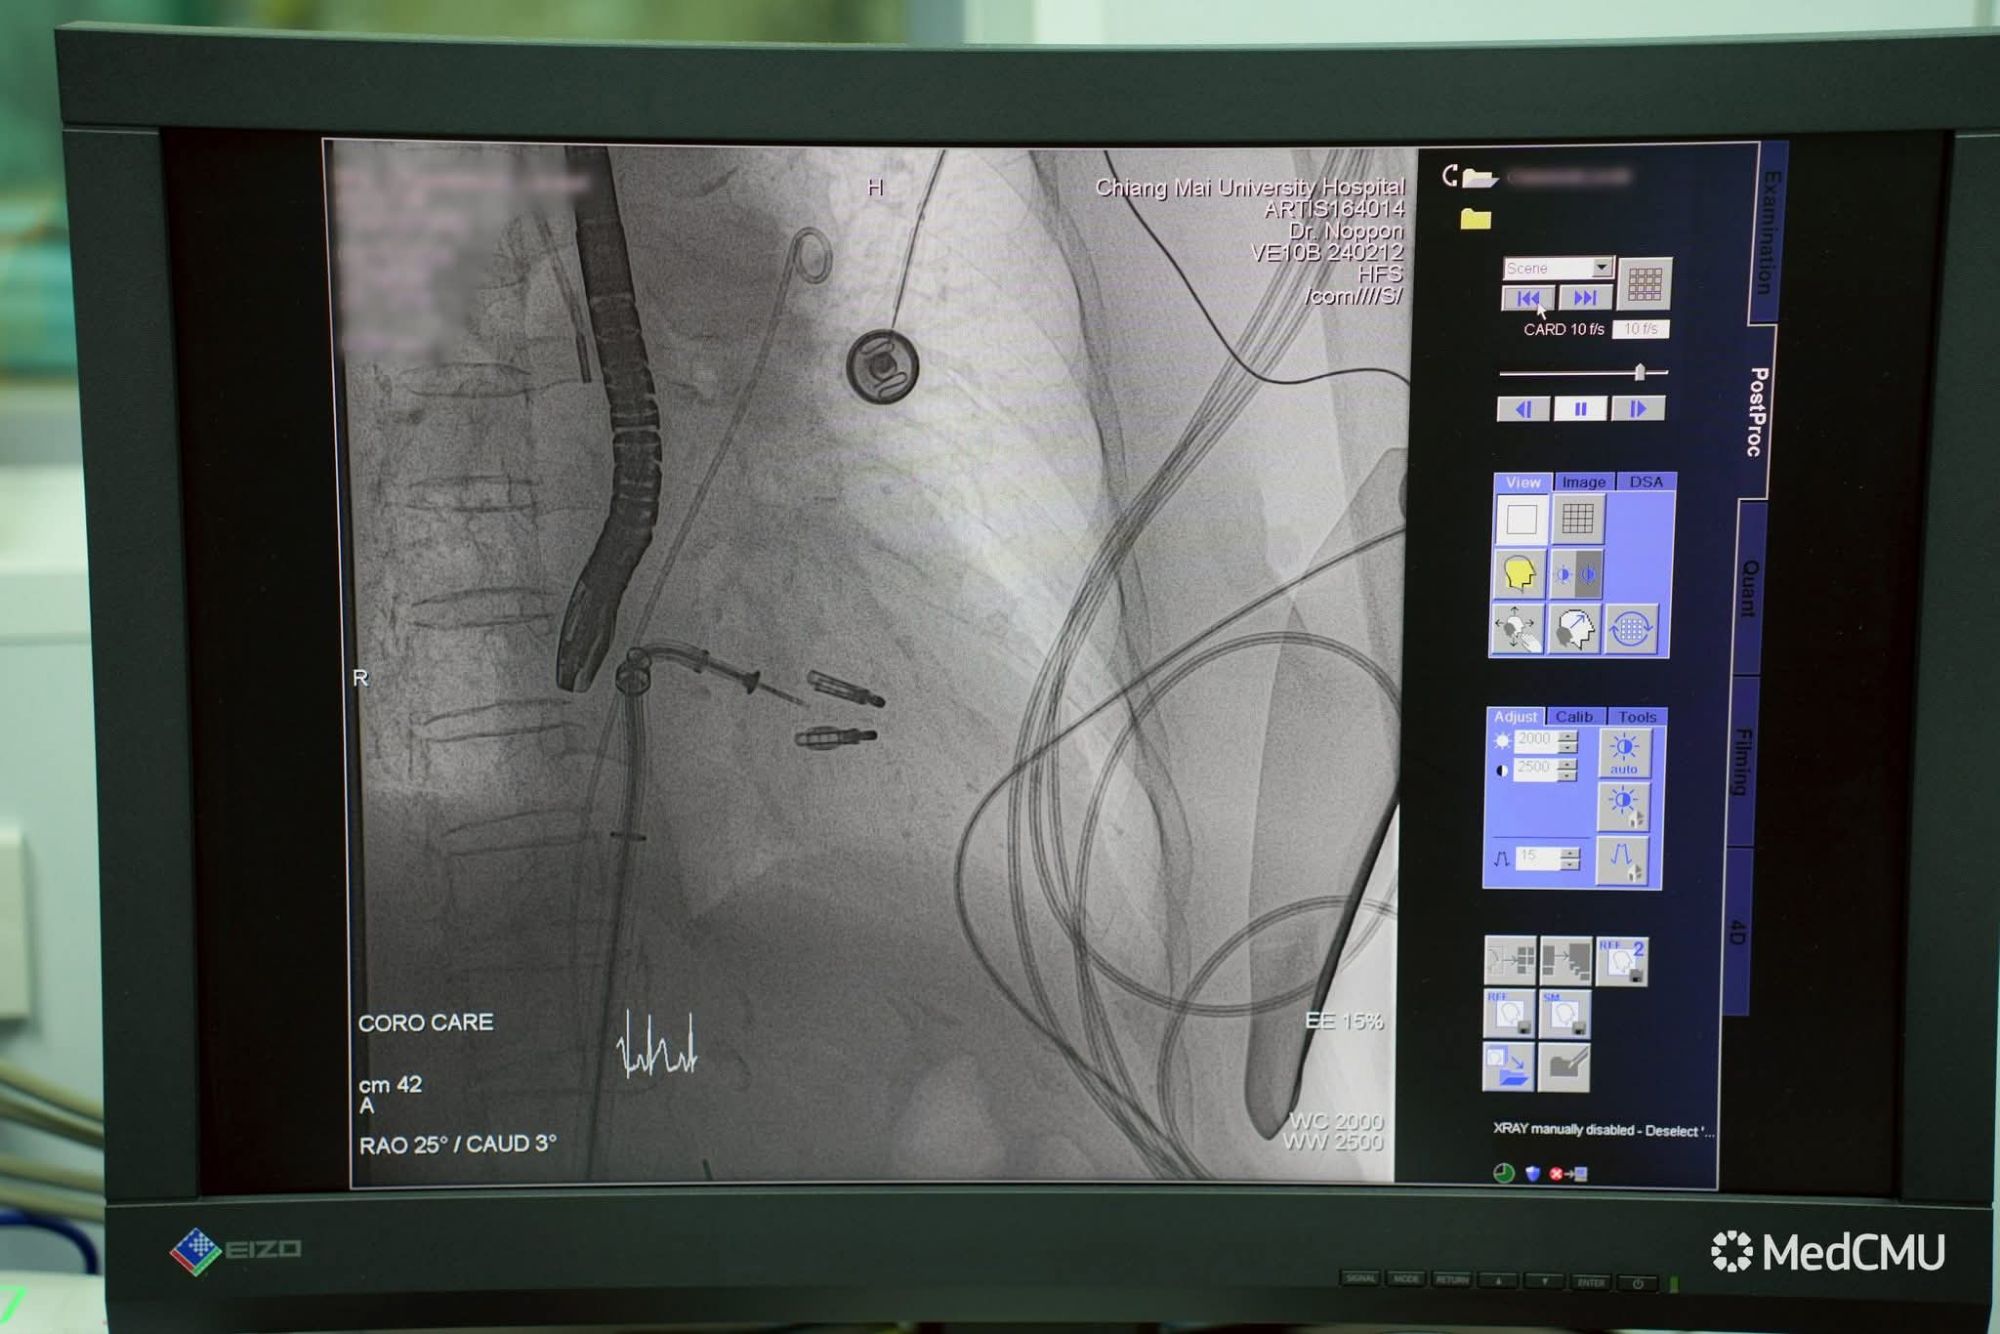

เทคนิค MitraClip เป็นนวัตกรรมการรักษาที่ใช้คลิปขนาดเล็กหนีบลิ้นหัวใจไมตรัลทั้งสองด้านให้ปิดแนบกัน โดยสอดคลิปผ่านสายสวนจากหลอดเลือดดำบริเวณขาหนีบ แทนการผ่าตัดเปิดหน้าอก วิธีนี้ช่วยให้เลือดไม่ไหลย้อนกลับ ลดภาระการทำงานของหัวใจ และผู้ป่วยสามารถฟื้นตัวได้รวดเร็วโดยไม่ต้องใช้เครื่องหัวใจและปอดเทียม

สำหรับเคสแรกนี้ เป็นผู้ป่วยหญิงอายุ 85 ปี มีภาวะหัวใจวายเฉียบพลันและต้องใส่ท่อช่วยหายใจกว่า 10 วัน เนื่องจากเส้นเอ็นยึดลิ้นหัวใจฉีกขาด ส่งผลให้ลิ้นหัวใจรั่วอย่างรุนแรง ซึ่งด้วยอายุและโรคร่วมหลายโรค ผู้ป่วยรายนี้ไม่เหมาะกับการผ่าตัดใหญ่ ทีมแพทย์หัวใจโรงพยาบาลมหาราชนครเชียงใหม่จึงตัดสินใจใช้เทคนิค MitraClip แทนการผ่าตัดเปิดหน้าอก

การรักษาใช้เวลาประมาณ 2–3 ชั่วโมง โดยใส่คลิปเพียง 2 ตัว หลังหัตถการ ผู้ป่วยสามารถถอดท่อช่วยหายใจได้ในวันถัดมา อาการเหนื่อยลดลงชัดเจน และมีแนวโน้มกลับบ้านได้ภายใน 1 สัปดาห์

เทคนิค MitraClip ได้รับการยอมรับและใช้กันอย่างแพร่หลายทั่วโลกมากว่า 15 ปี โดยให้ผลการรักษาใกล้เคียงกับการผ่าตัดในผู้ป่วยที่เหมาะสม ปัจจุบันในประเทศไทยมีเพียงไม่กี่ศูนย์ที่สามารถทำหัตถการนี้ได้ เนื่องจากต้องอาศัยทีมแพทย์เฉพาะทาง เครื่องมือขั้นสูง และความชำนาญในการทำอัลตราซาวนด์หัวใจผ่านหลอดอาหารเพื่อใช้เป็น “ดวงตานำทาง” ระหว่างทำหัตถการ